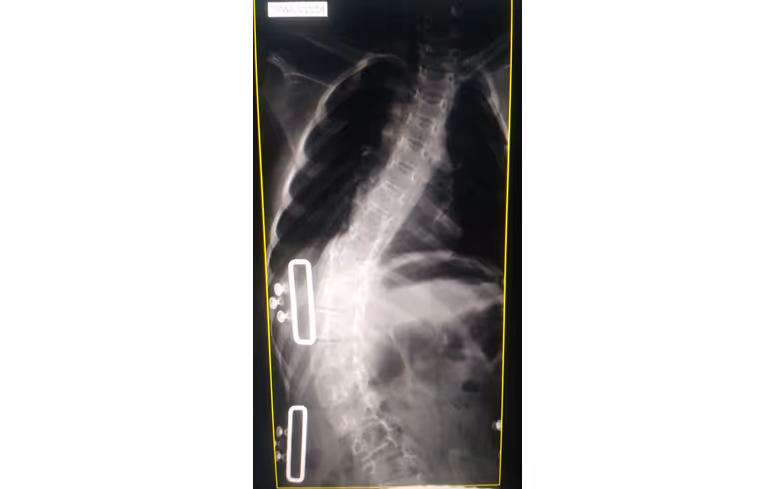

Сколиоз — деформация позвоночника в нескольких направлениях сразу: он будто пытается скрутиться спиралью. У пациентов со СМА встречается более, чем в половине случаев. Среди детей со СМА 1 и 2 типов — почти в 90% случаев [1].

Сколиоз может появиться в любом возрасте. У пациентов со СМА он формируется довольно рано и ухудшается по мере роста ребенка, поэтому важно обследовать пациента сразу, как только ему поставят диагноз СМА. Если есть признаки сколиоза, выполняется рентгенография позвоночника в двух проекциях [3]. Если деформации выражены или быстро развиваются, такое обследование нужно проходить каждые полгода.

при выраженном сколиозе (более 50 градусов);